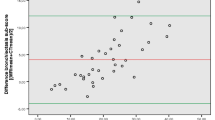

Dynamic change of cross-sectional area (cm2) in upper trachea in a COPD patient and in a volunteer. The time unit in the x-axis is the image number, while the frame time is 150 ms. Note that the curves show several respiratory cycles. The COPD patient demonstrated two different amplitudes in cross-sectional tracheal lumen during the first, and the two following cycles. However, the amplitudes in the three depicted respiratory cycles of the volunteer are quite uniform

The relative collapse of the trachea resulted in a median of 42% (range 20–83%) in volunteers and 64% (range 29–100%) in COPD patients (P=0.011). That means a collapse by 2/5 of the lumen in volunteers and by 3/5 of the lumen in COPD patients (Fig. 6) [(Table 1)].

Due to the semiautomatic measurement of the cross-sectional tracheal lumen, curves of the respiratory cycle were evaluated (Fig. 3). An oscillation became obvious with a frequency of about 10–15 min−1 (i.e., 25–40 images at 150 ms), which appears to correspond to a typical respiration frequency. However, due to the lack of respiratory registration this connection remains uncertain (Fig. 3). In the visual assessment of these curves, two different amplitudes have been detected in 8 out of 23 COPD patients, whereas the amplitude of the remaining COPD patients and all volunteers was uniform in visual assessment (Fig. 3). The median cross-sectional collapse of the trachea in this subgroup of eight COPD patients was 77% (range 37–95%) and was also significantly higher in comparison to the volunteers (P=0.002).

This can also be an explanation for the visually detected different amplitudes in 8 out of 23 COPD patients, while all volunteers demonstrated uniform respiration (Fig. 3). Even during the requested respiratory procedure, COPD patients incidentally breathe more deeply (had a sigh) [27, 28]. These findings influenced the calculation of tracheal collapse (Fig. 6). The breath-by-breath variability depended mainly upon irregularities in tidal breathing, and has also been described previously [27, 28]. Patients suffering from COPD not only have altered blood-gas and acid-base status, but also have different mechanical constraints to breathe and a different pattern of muscle recruitment for respiration as compared to normal subjects [27]. However, the variability between volunteers and COPD patients was not different, tested at rest and exertion [27]. However, the size of the subgroup identified in this trial appears to be too small for further interpretation. Furthermore, no online physiological data were recorded because this finding was beyond the horizon of this trial.